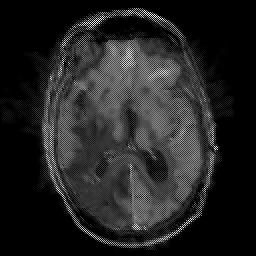

Glioma Overlay -- Slice #10

[Home][Help][Clinical] Slice 10